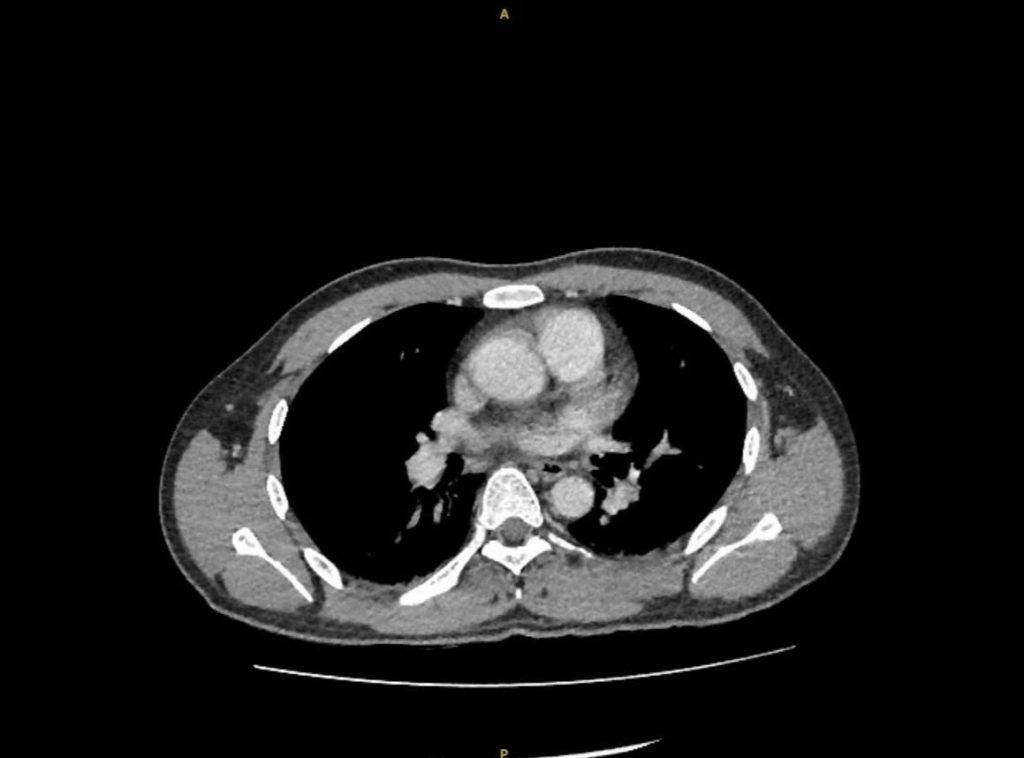

Tại bệnh viện, bệnh nhân lơ mơ, huyết áp tụt và sốt rất cao. Nhận định bệnh nhân đã rơi vào tình trạng chóng nhiễm trùng, các bác sĩ đã nhanh chóng vừa hồi sức vừa thăm khám và thực hiện các xét nghiệm chẩn đoán bệnh. Kết quả CT-scan bụng cho thấy có một viên sỏi nằm ở niệu quản trái đoạn lưng, gây tắc nghẽn hoàn toàn đường thoát nước tiểu – đây chính là thủ phạm khiến thận trái bị ứ và nhiễm trùng. Các xét nghiệm máu, nước tiểu và hình ảnh học cho thấy chỉ số nhiễm trùng tăng cao, có dấu hiệu thận trái đã bị ứ mủ và chức năng của thận bị suy giảm. Nguy hiểm hơn, tình trạng nhiễm khuẩn từ thận đã đi vào máu gây nhiễm trùng máu và có biến chứng choáng do nhiễm trùng, một biến chứng cực kỳ nguy hiểm có thể đe dọa tính mạng nếu không xử trí kịp thời.

Hình ảnh phim CT trước mổ cho thấy thận có sỏi niệu quản bị ứ nước